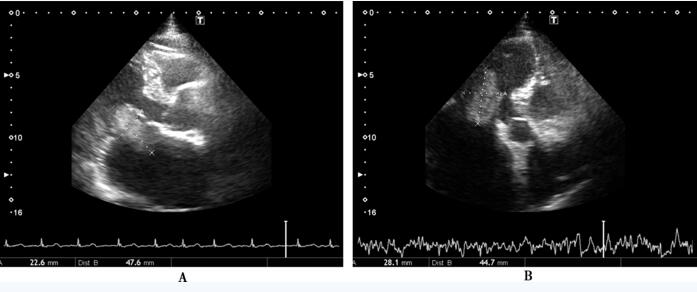

因超声心动图尚不能确诊左心房占位性病变为血栓或黏液瘤,故加用华法林口服抗凝治疗,剂量2.25~3.75mg/日,INR波动在1.2~3.0。请心外科会诊,考虑患者手术指征明确 (如为血栓,行取栓术;如为左心房黏液瘤,行黏液瘤切除术),拟行手术治疗。术前冠脉造影所见:右冠状动脉优势型;左主干正常;左前降支近中段可见明显钙化、弥漫长病变,狭窄50%~75%;左回旋支近段细小、狭窄25%;右冠状动脉近段狭窄50%,中远段内膜不光滑、全程钙化;左心室后支狭窄25%。后转入外科,于外科住院期间复查超声心动图发现左心房占位性病变消失,考虑为积极抗凝治疗后血栓消失 (图75-2),取消手术,出院后继续抗凝治疗。

图75-2 抗凝治疗后超声心动图

A:胸骨旁长轴切面未见左心房占位性病变;B:心尖四腔切面未见左心房占位性病变